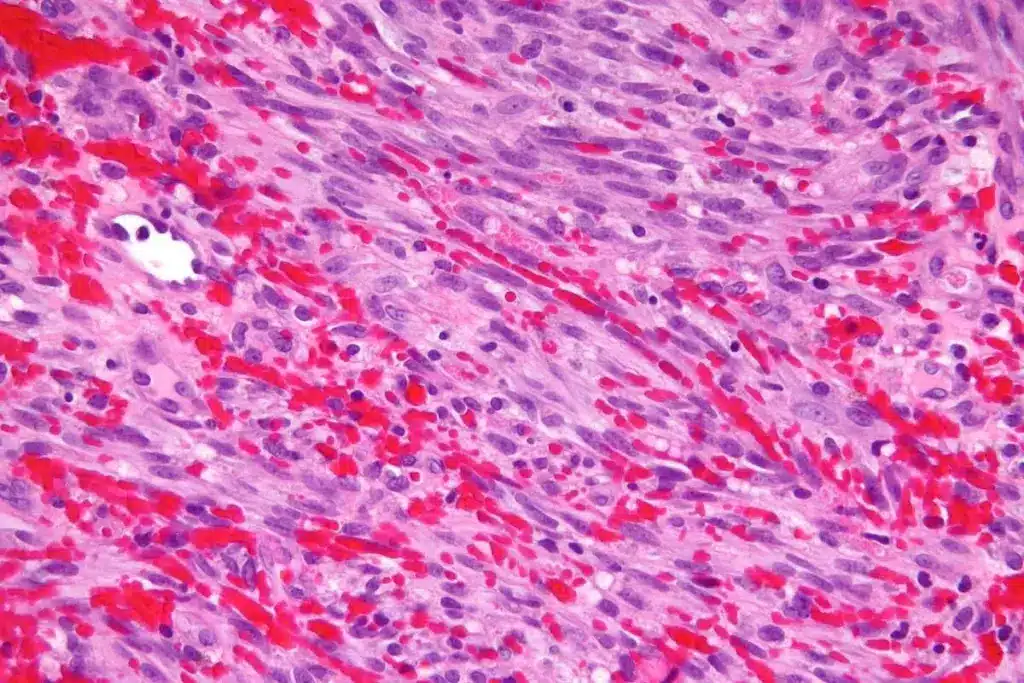

Visual Progression of Healing Skin Biopsies

The healing stages include redness and swelling first. Then, scabbing happens, and redness fades. Keeping the area clean and following doctor’s advice is key.

- Initial Stage: Redness and swelling

- Intermediate Stage: Scabbing and gradual reduction in redness

- Final Stage: Fading of the scar over time